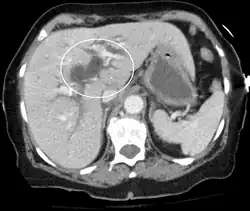

Ces examens sont distingués en non-invasifs et invasifs. Les examens non-invasifs sont utilisés en première intention, dans le but d'évaluer une obstruction des voies biliaires, l'état du foie et du pancréas, l'état vasculaire… Il s'agit de :

- l'échographie abdominale avec doppler.

- IRM abdominale et biliopancréatique.

- Tomodensitométrie abdomino-pelvienne avec injection.

Plus risqués, et selon des indications particulières (nécessité de ponction ou de biopsie ou à visée thérapeutique) sont des examens invasifs tels que l'échoendoscopie et différents types de cholangiographie (en)[12],[14].